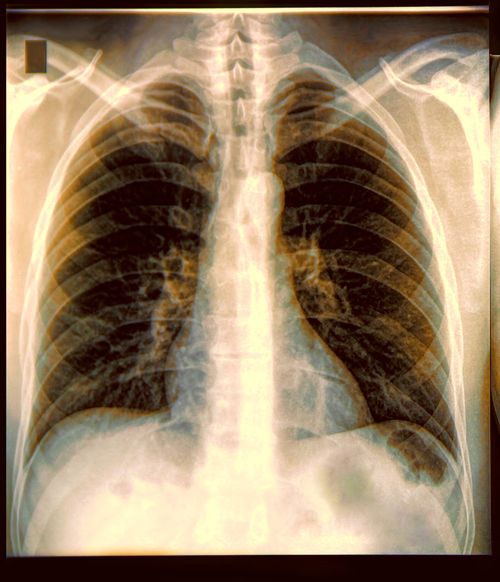

Diagnoses: Pulmonary bleb

Your best resource is a physician, preferably a pulmonologist, trained in dive medicine. A physician without the relevant experience may be thinking in terms of above-water activities and may not recognize the inherent dangers of breathing compressed gas at increased atmospheric pressure. A physician familiar with dive medicine would not likely give medical clearance to an individual diagnosed with a pulmonary bleb, which is a small blister or pocket of air trapped between the lung and the outer surface of the lung (visceral pleura). These spots are weaker than the normal lining of the lung and can occasionally break and cause air to leak from the lung into the chest cavity. A person who has pleural blebs usually has more than one, and all blebs are prone to leak at some time.

Since barotrauma can occur with hyperinflation of lung tissue, a diver's lungs must be able to tolerate rapid changes in volume and pressure. Any weakness in lung structure or architecture may be predisposed to rupture from even slight overinflation in an otherwise healthy person. Pulmonary barotrauma, which can lead to rupture of the lung air sacs (alveoli), usually happens toward the end of a dive, even a shallow one. Escaping gas can enter one of four places: the subcutaneous tissues of the neck and chest wall; the area around the heart, causing pneumomediastinum (mediastinal emphysema); the pleural space between the lung and chest wall, causing pneumothorax; or the bloodstream, causing arterial gas embolism (AGE).